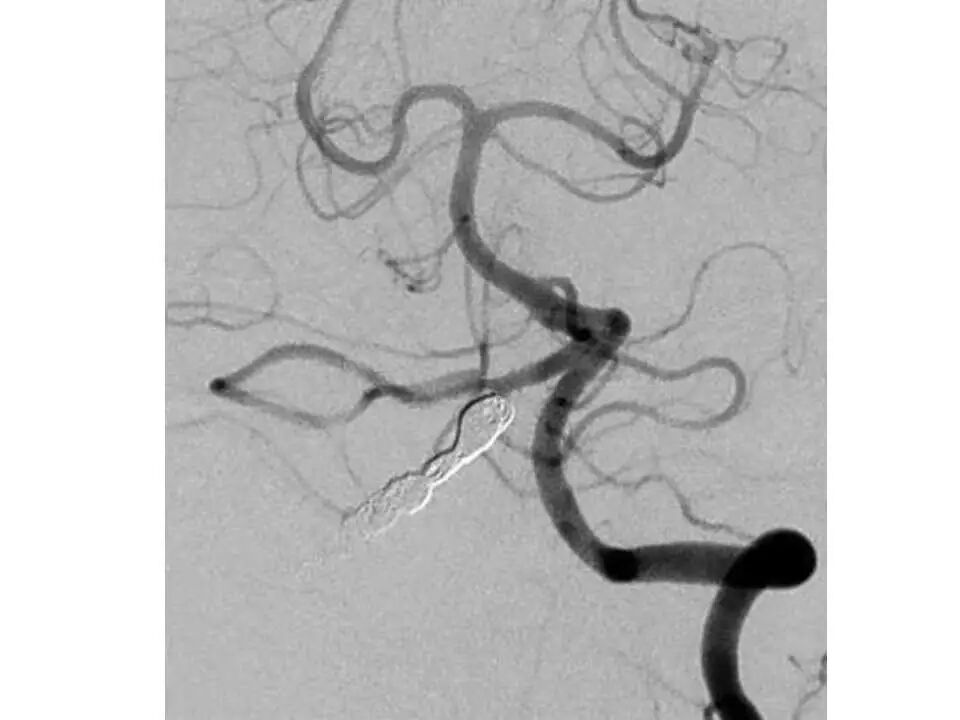

今天为大家分享的是“强生医疗CNV-神经介入专栏”第十五期,由首都医科大学宣武医院何川教授带来的“颅内动脉瘤介入治疗”精彩讲课视频及PPT,欢迎观看、阅读。文章仅代表作者个人观点,如有不同见解,欢迎同道斧正!

何川 ,首都医科大学宣武医院副主任医师,中国医师协会神经介入专业委员会常务委员,长期从事脑血管病和脊髓血管病的手术及介入治疗和相关研究工作。首都医科大学神经外科博士,师从于中国神经介入开创人凌锋教授;日本东北大学医院脑血管病治疗科博士后,师从于日本国脑血管病血管内治疗的开创者高桥教授。